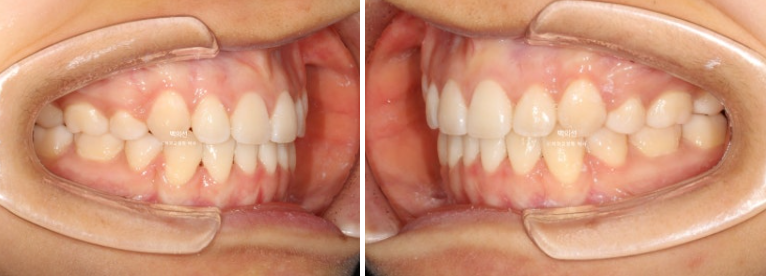

23년 7월 교정을 위해 내원한 환자분입니다.

덧니가 심한 편 입니다.

잇몸이 얇아서 20대 초반의 나이임에도 불구하고 덧니를 포함한 일부 치아의 잇몸이 내려가 있습니다.

군데군데 잇몸이 내려가 뿌리 노출된 부분들이 있습니다.

덧니 펼 공간이 많이 필요하고 잇몸도 얇아 비발치로 치료 시 잇몸이 더 내려갈수도 있는 상태입니다.

초진 입매를 보면 입술돌출은 거의 없지만 상기의 이유로 작은어금니 4개 발치교정을 결정하였습니다